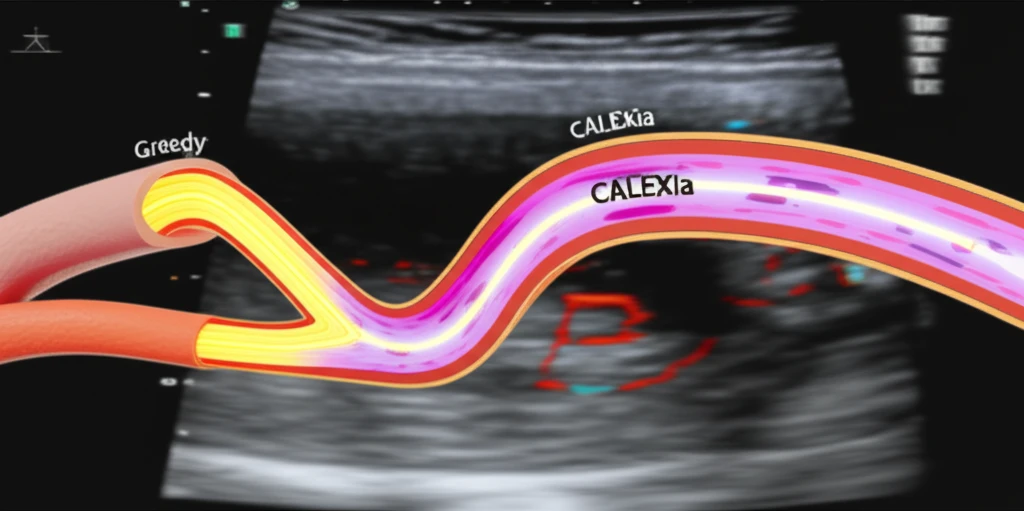

Researchers developed two distinct automated techniques for segmenting carotid arteries in ultrasound images: CULEXsa (Completely User-independent Layer EXtraction based on signal analysis) and CALEXia (Completely Automated Layers EXtraction based on integrated approach). CULEXsa relies on local statistics and signal analysis, while CALEXia integrates feature extraction, line fitting, and classification.

- Starting Point: The greedy technique begins with the method demonstrating lower system error – CULEXsa for the LI boundary and CALEXia for the MA boundary.

- Iterative Swapping: The algorithm iteratively swaps vertices (points) of the profiles from the two techniques, assessing the overall distance to a manually traced "ground truth" boundary by experts.

- Minimization: The process continues until the overall distance to the manual boundary is minimized.

- Fusion: The final boundary, dubbed the "Greedy boundary," consists of points strategically selected from both CULEXsa and CALEXia segmentations.